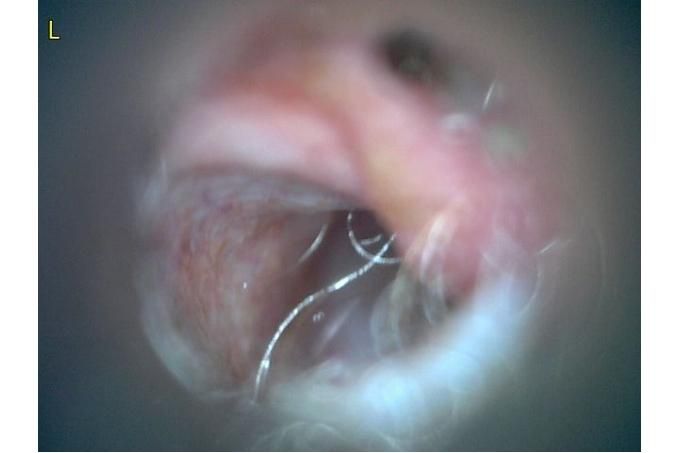

오늘 낮과 방금 5분전에 일어난 일인데요.. 강아지 귀질환 중에.. 옷입히고나서 귀를 바닥에 대고 비비거나, 귀에 통증을 호소하면서 잠깐 비틀비틀 걷는 경우 이런 경우 대체 뭘까요? 외이염일때도 이럴수도 있을까요? 아니면 중이염 내이염일지.. 한 2~3분정도 통증을 호소하다 지금은 또 정상이 됬는데 옷입을때만 옷의 목카라 부분이 귀에 닿을때 문제가 되는 느낌입니다. 평상시엔 가끔 양쪽 귀를 긁거나 귀를 자주 터는 정도입니다. 특이사항은 오른쪽귀 솜 돌돌 말아 귀안에 넣어줘도 비명을 지르며 엄청 아파하는데(작년11월경) 왼쪽은 안아파합니다)

그리고 용종이라고 코멘트 달아주셔서 저 검이경 사진 찍은곳에 물어보니 용종은 아니라고합니다.

mri ct 말고는 죽어도 중이염 내이염 또는 고막 확인이 불가능한가요?

저 부분 용종 아니라합니다

제가 가장 알고싶은점은. 저렇게 옷깃에 귀가 시쳐도 아파할정도면 이게 외이염일까요 중이염일까요 내이염일까요? 얼마나 아픈지 옷한번 얇은 내복 평상시 입던거 입히면 입히고 나서 바로 온집을 돌아다니면서 바닥에 귀를 대고 정신나간애처럼 비비고 비틀비틀 걷습니다 그러다가 2~3분후 다시 정상으로 돌아옵니다

(근데 또 귀를 조물락 조물락 만져도 안아파합니다, 다만 솜을 길게 해서 넣으면 솜만 넣어도 아파합니다 특히 오른쪽요 왼쪽은 안아파합니다)